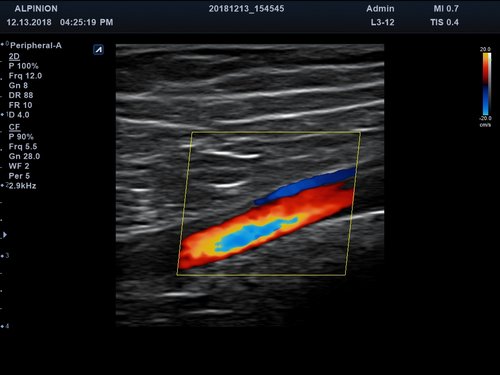

Anwendungsbereiche Abdomen MSK, Nerven, Karotis, periphere Gefäße, Schilddrüse, Mamma

Bildgebungs-Modi B-Modus, CF, M, PW, PD B-Modus, CF, M, PW, PD

• Farbdoppler: farbige Darstellung der Richtung des Blutflusses